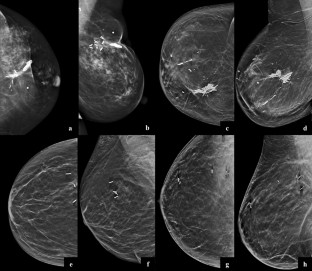

Fig. 1

Fig. 2

Fig. 3